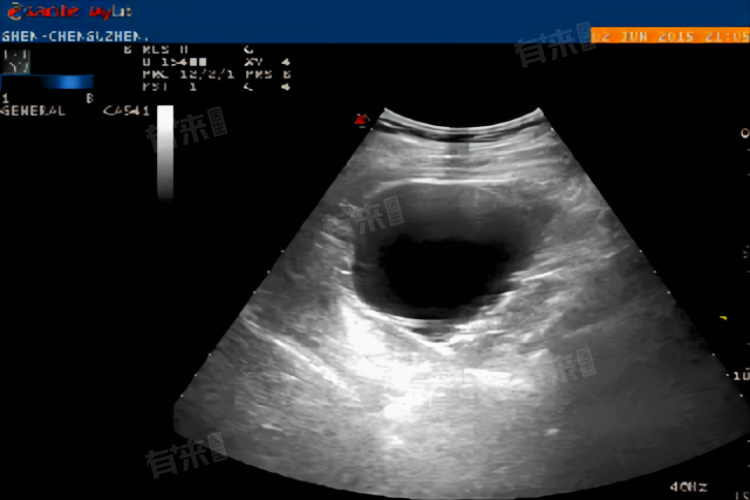

从超声检查的原理来讲,超声探头发出的超声波在人体组织中传播,当遇到不同声阻抗的组织界面时会发生反射,这些反射信号被探头接收后转化为电信号,经过处理形成超声图像。而无回声区域的出现,说明超声波在这个区域没有遇到明显的组织界面,或者说这个区域内的物质对超声波的反射能力非常差。

- 在检查充满液体的结构时,如正常的胆囊,胆囊内充满胆汁,胆汁是一种相对均匀的液体,其内部几乎没有能让超声波产生明显反射的界面。所以在超声图像上,胆囊内部通常呈现无回声区。同理,当正常的膀胱里面充满尿液时,尿液也是均匀的液体,超声图像中膀胱内部也会显示为无回声。

- 但是,无回声区域并不一定都代表正常的液体结构,在一些病理情况下也会出现。比如当身体某个部位出现囊肿时,囊肿内部通常是液体,这些液体成分在超声检查下也会表现为无回声。但是囊肿的存在可能会对周围组织产生压迫等不良影响,所以即使是无回声,也需要进一步分析大小、位置、边界以及与周围组织的关系等因素。

当看到检查报告中有无回声这样的描述时,不能简单地认为一定是正常或者不正常,这需要结合检查的部位、无回声区域的具体特征以及其他检查结果来综合判断。如果对无回声区域的情况感到担忧,可以向医生详细询问,了解其可能代表的具体意义,更好地把握自己的健康状况。